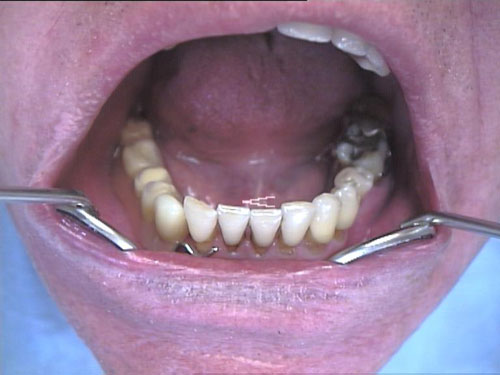

Zahnimplantate 1